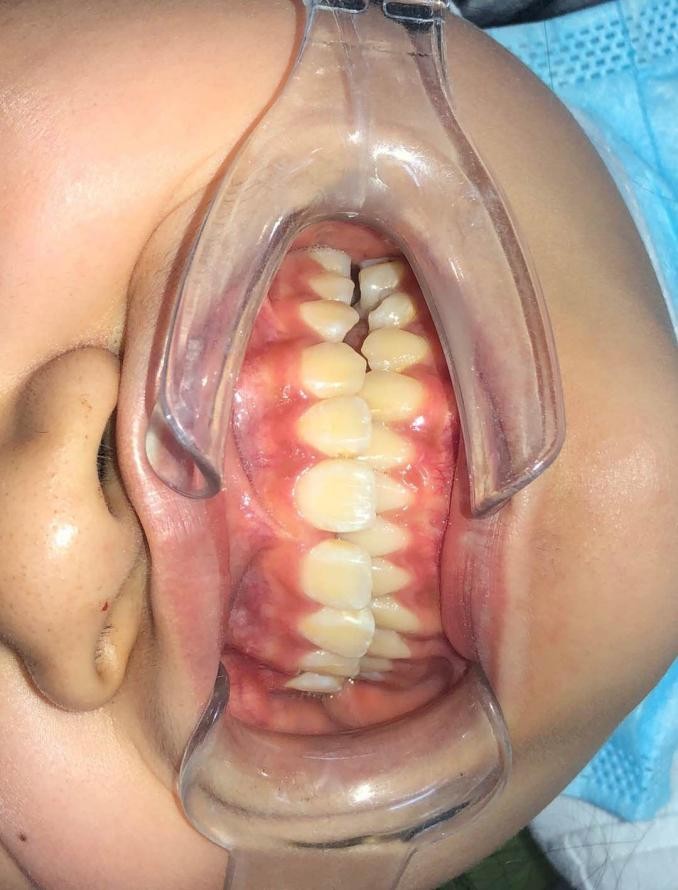

患儿的面像、口内情况如图所示。

可以看到患儿的下巴是偏斜的,面部不对称。经检查发现患儿口内可见多颗乳磨牙龋坏,有偏侧咀嚼习惯,存在颌骨发育的不对称。这种严重的骨性畸形需要双期矫治。第一期早期矫治,其目的是去除病因及干扰因素,让上下颌骨的生长导向正常,从矢状向、横向、垂直向去改善上下颌骨的不调。该患儿首先应用的是矫形力矫治器(螺旋扩弓器),协调上下颌骨宽度,去除锁合侧咬合干扰,建立双侧后牙咬合,治疗乳磨牙龋坏,同时指导患儿用双侧咀嚼食物促进咀嚼肌平衡发育。然后应用的是FRⅢ功能矫治器,解除前牙反合改善下颌偏斜,FRⅢ的作用原理是去除导致颌骨畸形的功能因素而且可以改善轻度的骨性错合。

下图为早期矫治前后面型和口内像对比,可以看到矫治后的患儿面型左右基本对称,下牙列的偏斜程度也明显改善,前牙的反合得到解除,去除了上颌骨发育的不利因素。接下来就是等待患儿换完牙以后进行二期治疗,二期治疗可以从三维方向上控制牙齿的移动方向,进一步平衡咬合,使得矫治效果更加稳定。二期治疗的矫治器可以选择固定矫治器也可以选择无托槽隐形矫治器。